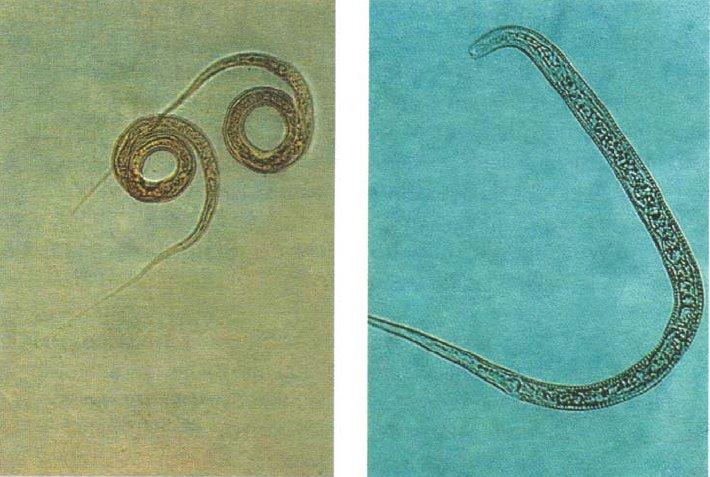

Фотографии нематод, цестод и трематод в природе

Раздел: Другие животные